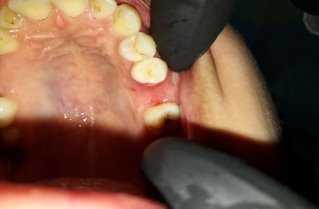

Техника пластики проводилась таким же путем как описано выше. (рис 2)

В послеоперационном периоде для профилактики воспалительных осложнений были назначены антибиотики и противовоспалительные препараты, и была предупреждена в день операции не принимать горячую ванну, курить, избегать резкого физического напряжения, вызывающего повышение артериального давления. Швы были сняты через 7 дней.

Рис. 3. Вид через 1 месяц